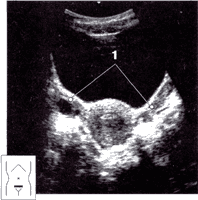

Еще недавно широко применялось обследование УЗИ через переднюю брюшную стенку с максимальным наполнением мочевого пузыря - своеобразным акустическим "окном", через которое можно увидеть исследуемые органы. Сейчас многократно используют трансвагинальный датчик, вводимый при осмотре во влагалище. При близком расположении к исследуемым органам получают более качественное изображение, что позволяет не наполнять мочевой пузырь.

Диагностируют беременность на УЗИ, используя трансвагинальный датчик, при задержке менструации 3-5 дней (срок 4,5 недели, если считать от первого дня последней менструации). На этом сроке в полости матки можно визуализировать плодное яйцо диаметром, равным в миллиметрах примерно числу дней задержки.